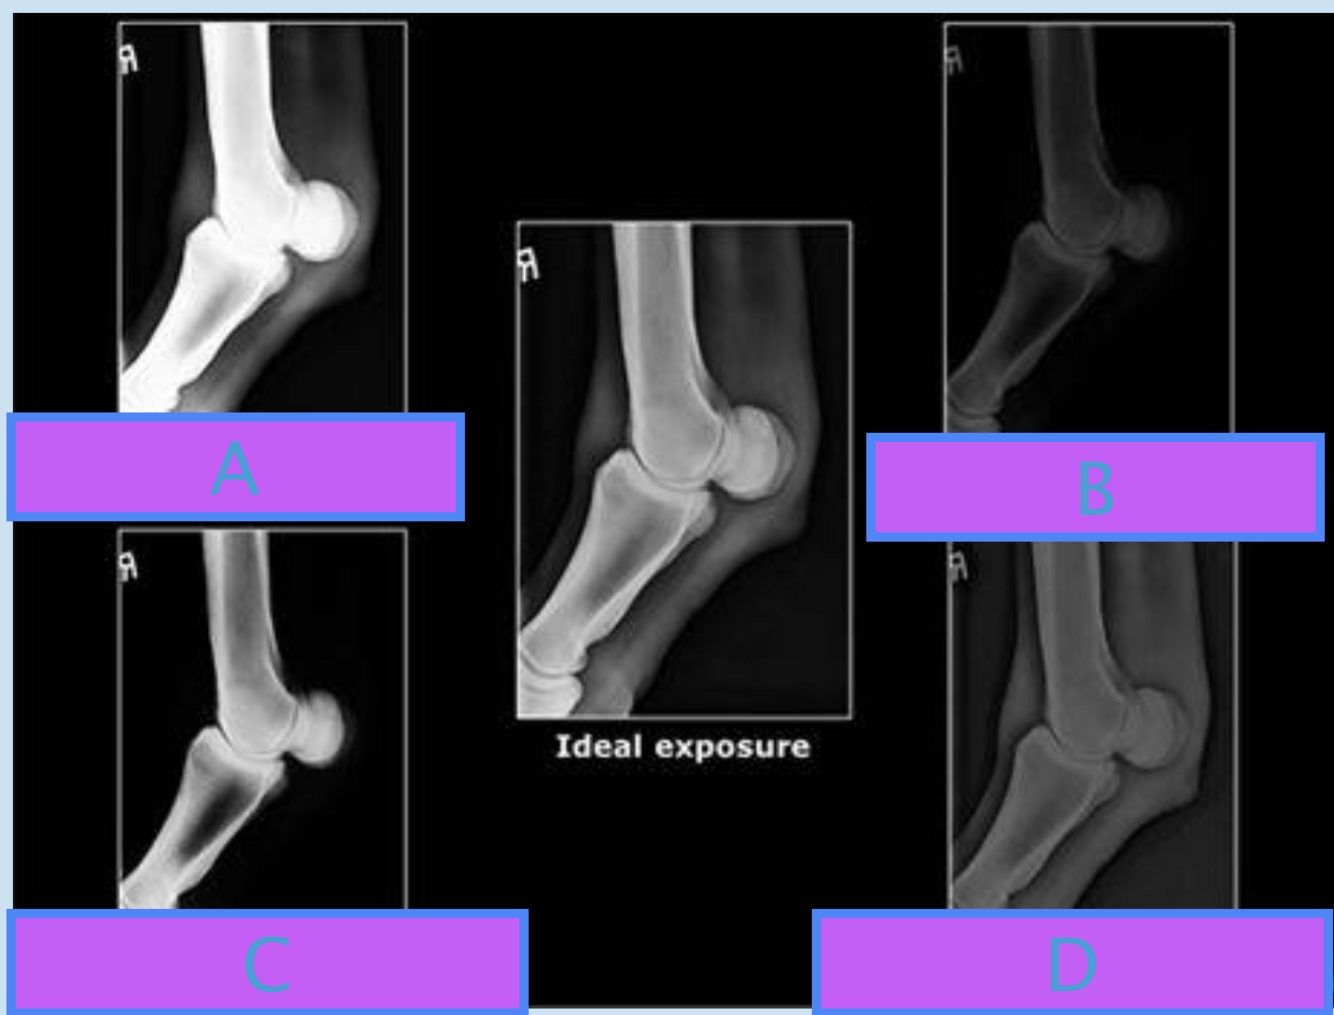

A

A Underexposed - mAs low

B

B Overexposed - mAs high

C

C Increased contrast - kv low

D

D Decreased contrast - kv high